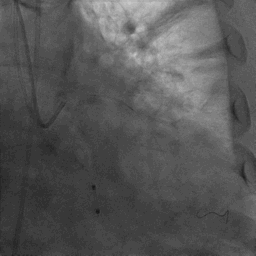

复查冠脉造影结果满意

造影提示微少量返流,压力监测提示主动脉瓣压差7mmHg